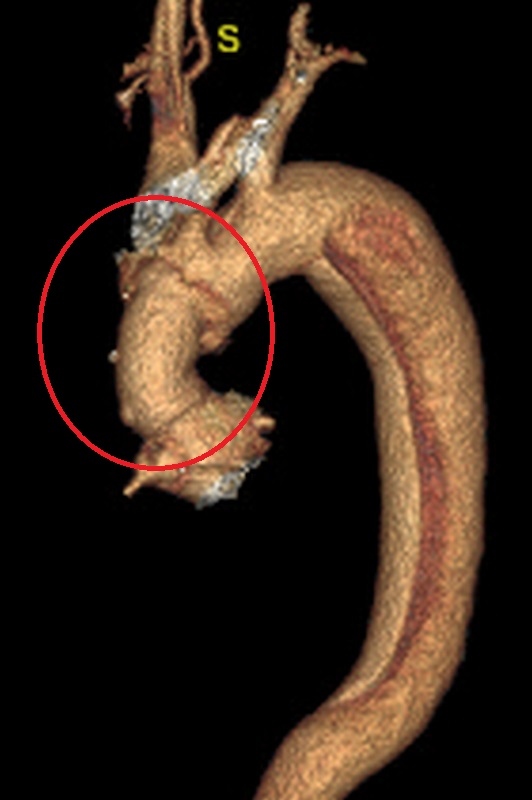

▲術後。